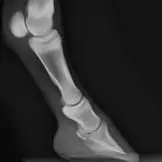

Die Anwendungsbereiche für röntgenologische Untersuchungen sind sehr vielfältig. Fast jede Lahmheitsuntersuchung und orthopädische Untersuchung erfordert die röntgenologische Darstellung bestimmter Gliedmassenabschnitte in mehreren Ebenen. Nahezu jede Kaufuntersuchung beinhaltet neben der klinischen Untersuchung auch die Erstellung von Röntgenbildern der Gliedmaßen und in vielen Fällen auch der Oberlinie. Bei bestehenden Rittigkeitsbeschwerden wird häufig eine Röntgenuntersuchung des Halses und des Rückens vorgenommen. Aufgrund der Leistungsstärke unserer Röntgenanlagen ist es uns häufig möglich, auch den Beckenbereich des Pferdes inklusive Hüftgelenk am stehenden Pferd zu untersuchen.